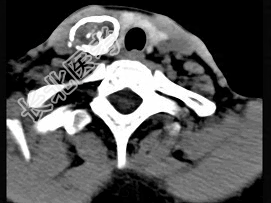

- 多项选择题50岁女性患者,体检发现右侧甲状腺有较硬结节, CT扫描如图所示,请选择正确的描述和答案 ( )

A、右侧甲状腺内见稍低密度影,周边围以环形致密钙化影

B、肿块影与周围结构分界清楚

C、考虑为结节性甲状腺肿

D、考虑为甲状腺癌

E、考虑为甲状腺腺瘤钙化